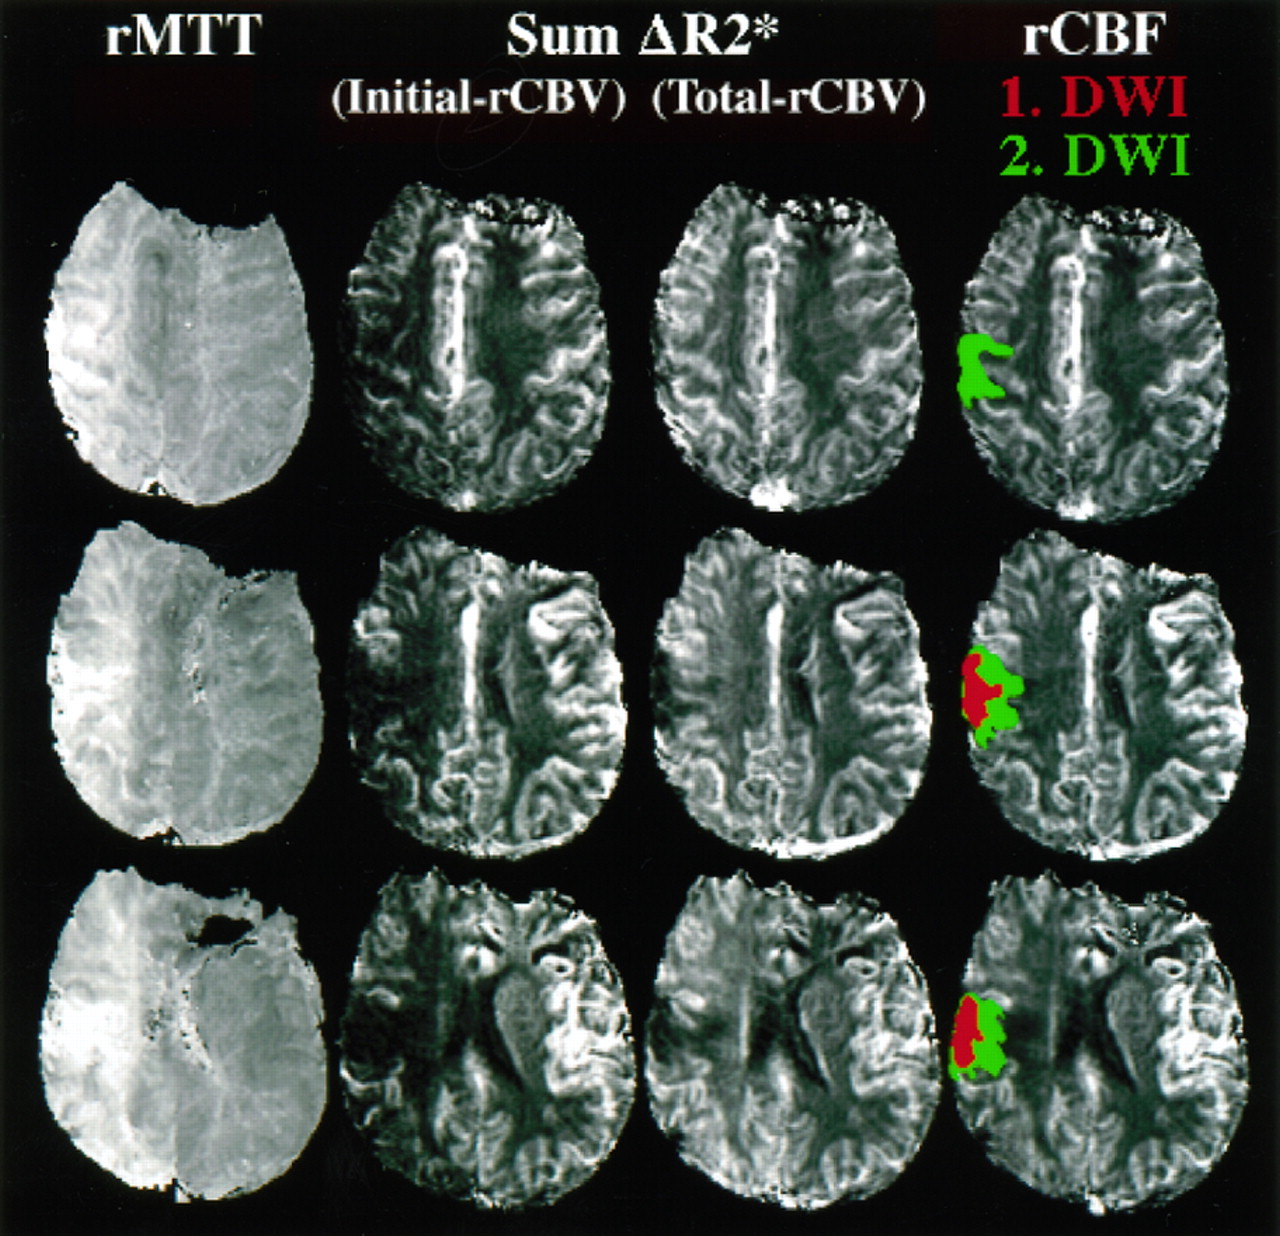

图2。这个图展示了水平切片两种不同脑血容量cb v()都未地图(cb v初始相对[rCBV],都未总rCBV),相对平均运输时间(rMTT)地图,和一个图像代表相对脑血流量(rCBF)。看到更多的细节关于这些图片的方法计算。

之间的各种估计rCBV,最初的操作半影rCBV是最好的预测。最初rCBV反映曲线下的面积曲线的初始部分,因此指数加权的rCBV流入血液的体积。最初rCBV非常类似于rCBF在这项研究中,这中可以看到图2而在表1显示类似的比例差异半影和缺血性核心定义的操作。虽然最初的rCBV显著降低,总rCBV显著增加的运营半影侧控制区域。然而,总rCBV不如最初rCBV差异化运营从缺血半影的核心。rCBV总数的增加在我们的操作半影同意大多数宠物cb v测量显示增加缺血半影中都未引起的早期代偿反应脑灌注压降低。12,13rCBF略优于初始rCBV在区分半影从核心定义的操作。rMTT显著延长操作半影,更在缺血性核心。然而,rMTT是不如其他标记区分从缺血半影核心定义的操作,但在区分异常(即是一个优秀的标志。,核心和半影)从正常灌注(见表1)。